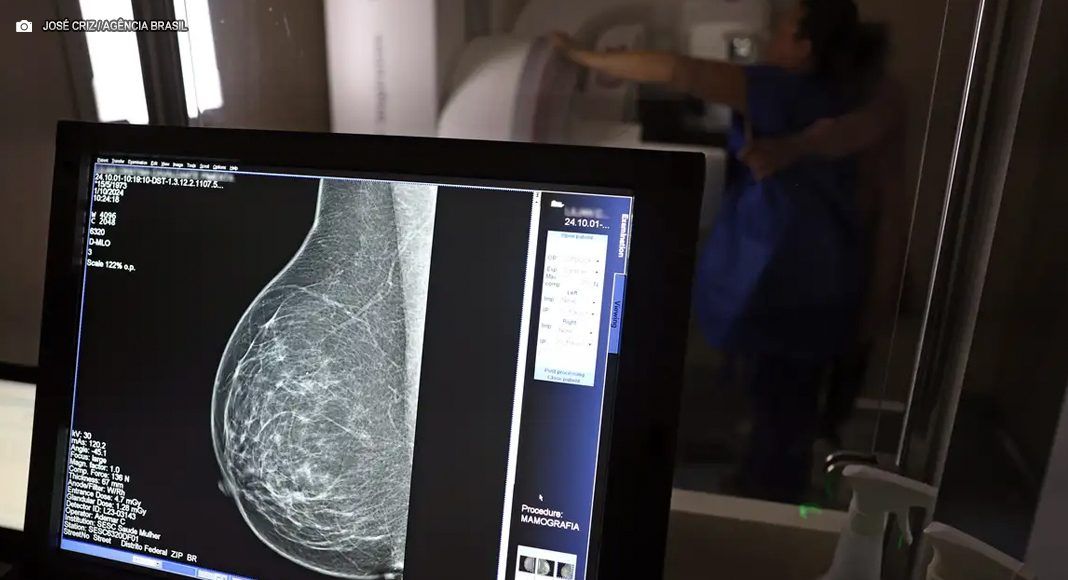

A partir de quantos anos se deve fazer a mamografia de rastreio, ou seja, como um exame de rotina, mesmo sem sintomas? Para autoridades públicas, como o Ministério da Saúde e o Instituto Nacional do Câncer (Inca), o ideal é que a mamografia seja feita a cada dois anos por todas as mulheres entre 50 e 69 anos. Algumas entidades médicas, como a Sociedade Brasileira de Mastologia (SBM), entretanto, recomendam exame anual a partir dos 40 anos.

Entre os critérios para que as operadoras de planos de saúde sejam certificadas, está a realização de exames de rastreamento de diversos tipos de câncer, o que contribui para o diagnóstico precoce. No caso do câncer de mama, a minuta elaborada pela ANS estabelece o rastreamento organizado, com a convocação de todas as beneficiárias dentro da faixa etária para fazer a mamografia e outros exames complementares que forem necessários.

A ANS decidiu, entretanto, seguir em sua minuta o protocolo do Inca, que também é adotado no Sistema Único de Saúde (SUS) e preconiza a realização de mamografia de rastreio apenas a partir dos 50 anos, com intervalo de dois anos entre os exames, caso nenhum problema seja encontrado. “O rastreamento do câncer deve ser direcionado às mulheres na faixa etária e periodicidade em que há evidência conclusiva sobre redução da mortalidade por câncer de mama e em que o balanço entre benefícios e possíveis danos à saúde dessa prática seja mais favorável”, diz a minuta.

Roberto Gil explica por que esses estudos consideram que os 50 anos são a idade certa para o início do rastreamento na população em geral: “Não estamos negando que mulheres abaixo de 50 anos tenham câncer de mama. Estamos falando que, abaixo dos 50 anos, acumulam-se outros problemas e o rastreamento populacional é menos eficiente. A mamografia é um exame de raio X, que vai ser mais efetivo na medida que a mama seja menos densa e que se tenha mais contraste na imagem, para não se confundir o parênquima normal com um nódulo. Então [antes dessa idade], aumenta muito mais a possibilidade de ter falsos positivos e ter que fazer mais exames. Posso fazer uma biópsia e ser mais difícil interpretar e levar a uma cirurgia desnecessária.”